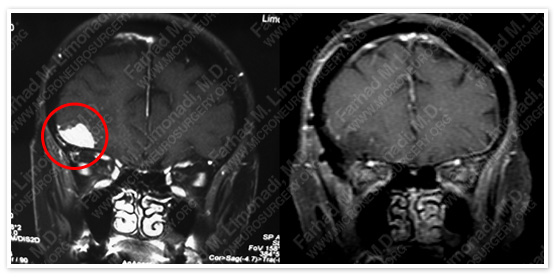

Before Operation                                              After Operation

Post -p MRI shows complete resection of the tumor with no injury to surrounding neurovascular structures.